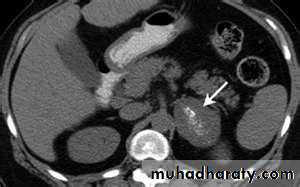

Phaeochromocytoma (adrenal paraganglioma)

A tumour of adrenal medulla, derived from chromaffin cells and produces catecholamines.

It represents 0.1–0.6% of hypertensive patients.

It is known as the ‘10% tumor’ as 10% are inherited, 10% are extra-adrenal, 10% are malignant, 10% are bilateral and 10% occur in children.

Investigation

1- elevation of adrenaline, noradrenaline, metanephrine and normetanephrine levels in a 24-hour urine collection.

2- imaging study for the localization of the phaeochromocytoma and/or metastases. MRI is preferred because contrast media used for CT scans can provoke paroxysms.